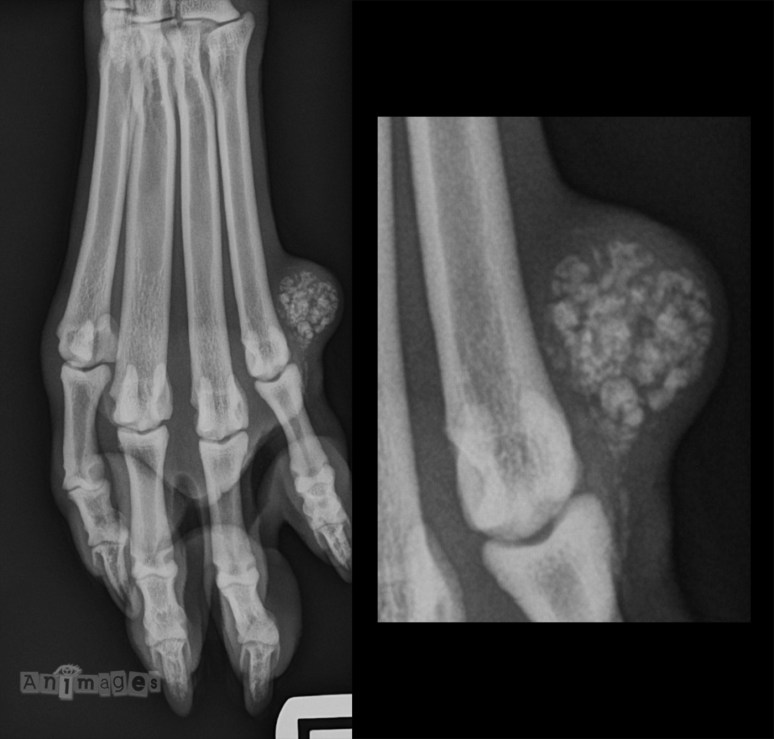

RadioQuiz 19 – Petite masse sur un pied

Signalement: Rottweiler mâle intact, 12 mois.

Présentation clinique: Masse indurée palpée du côté latéral du pied gauche que le chien s’est mis à lécher récemment.